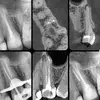

1991 yılında Bursa'da doğmuştur. 2009 yılında Bursa Fen Lisesi'nden 2014 yılında ise Bülent Ecevit Üniversitesi Diş Hekimliği Fakültesi'nden mezun olmuştur. 2012-2013 yılları arasında bir yıl süre ile Ege Üniversitesi Diş Hekimliği Fakültesi'nde klinik eğitim almıştır. 2016 yılında Diş Hekimliği’nde Uzmanlık Sınavı (DUS) ile İzmir Kâtip Çelebi Üniversitesi Diş Hekimliği Fakültesi Endodonti (Kanal Tedavisi) bölümünü kazandıktan sonra Sağlık Bakanlığı ve Tıpta Uzmanlık Kurulunun belirlediği teorik ve klinik eğitimleri başarı ile tamamlayarak Endodonti uzmanı ünvanını almaya hak kazanmıştır. Bursa, İstanbul ve İzmir olmak üzere özel polikliniklerde çalışma deneyimi bulunmaktadır. Halen müşterek muayenehanesinde Çocuk Diş Hekimliği uzmanı olan eşi ile birlikte çalışmaktadır. Mesleki ilgi alanları; kanal tedavisi yenilemesi (retreatment), endodontik cerrahi, kanal tedavisi görmüş madde kayıplı dişlerin direkt ve indirekt restorasyonu ile vital-devital beyazlatmadır. Kişisel ilgi alanları ise; CrossFit, basketbol ve bisiklet sporlarıdır.